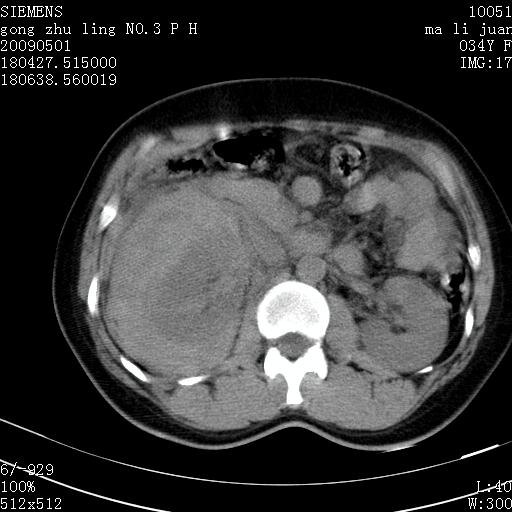

标题: CT19733:右肾碎裂 [打印本页]

标题: CT19733:右肾碎裂

青年女性,骑摩托车摔伤。

右肾碎裂伤,包膜下血肿。

术中仅见右肾碎裂,肾蒂血管未见断裂。

支持 右肾破裂伴肾包膜下及肾周血肿。

右肾破裂并右侧腹膜后间隙出血。